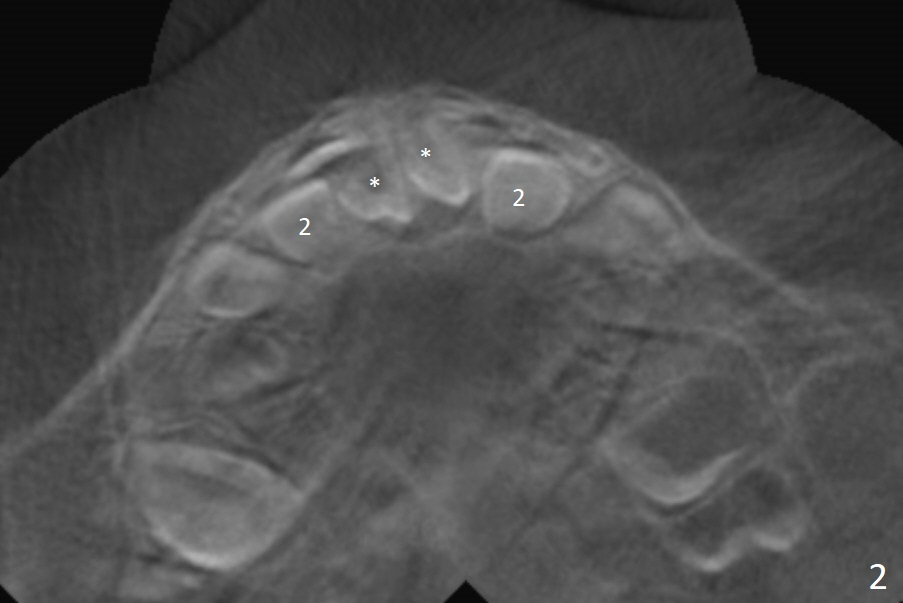

A 3-year-old boy with attention deficit and autism has several incipient caries.  Panoramic X-ray reveals that two of mesiodens (Fig.1 *) block eruption of the upper central incisors (1), as compared to the lateral ones (2).  When is the best time to extract the mesiodens?

CBCT taken on 11/03/2017 confirms the findings mentioned above (Fig.2-4).  These 2 supernumerary teeth are close palatally (Fig.3 (for UR1), 4 (UL1)).

Reanalysis of 3 D images (Fig.7 (frontal view), 8 (posterior view), 9 (lateral view), 10 (lateral view with section) of CT taken 1 year 3 months earlier shows that the mesiodens (*) and the permanent lateral incisors (2) are palatal to the permanent central incisors (1) and canines (3) and the deciduous central incisors (A).  The supernumerary teeth do block the eruption of the permanent central incisors (Fig.10).